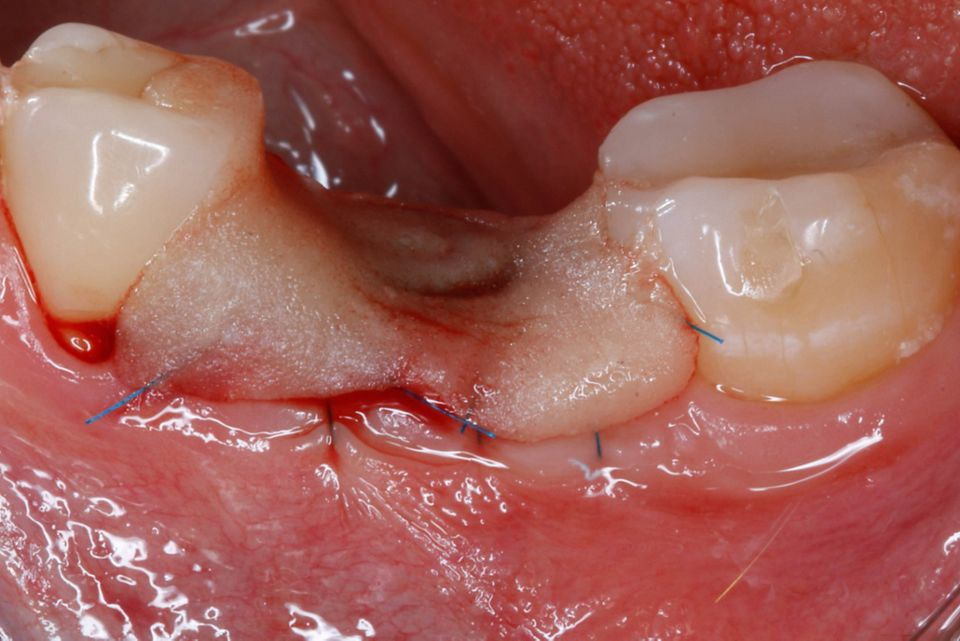

#36 牙的手术过程从局部麻醉和下牙槽神经阻滞开始。通过分割磨牙根实现无翻瓣反射的无创拔牙;从而保留肺泡壁和根间隔膜(图3-4)。仔细清洁牙槽,形成种植体路径并放置Straumann ® BLX 种植体 5.5 x 8 mm (图 5-7)。为了促进非浸没式愈合,将标准愈合基台连接至种植体。骨壁和种植体之间的间隙填充有同种异体骨材料颗粒(maxgraft®,botiss 生物材料,德国)。应用富含血小板的纤维蛋白(PRF)来实现适当的初步愈合。调整软组织边缘并用聚丙烯 6/0 缝合,使愈合基台暴露(图 8-9)。将粘性牙周Reso-Pac ®敷料(来自德国杜伊斯堡的Hager & Werken)放置在治疗区域上以协助愈合过程(图10)。

手术后一周,拆线(图11-12)。在同一次就诊时,拍摄了垂直牙科射线照片(图 13),显示种植体处于正确的修复位置。四个月后,愈合基台被移除。粘膜外观表明植入物周围有稳定且健康的软组织,具有足够的生物宽度和光滑的出现轮廓(图14-15)。取印模,一个月后,将最终的氧化锆陶瓷牙冠拧到种植体上(图 16-18)。